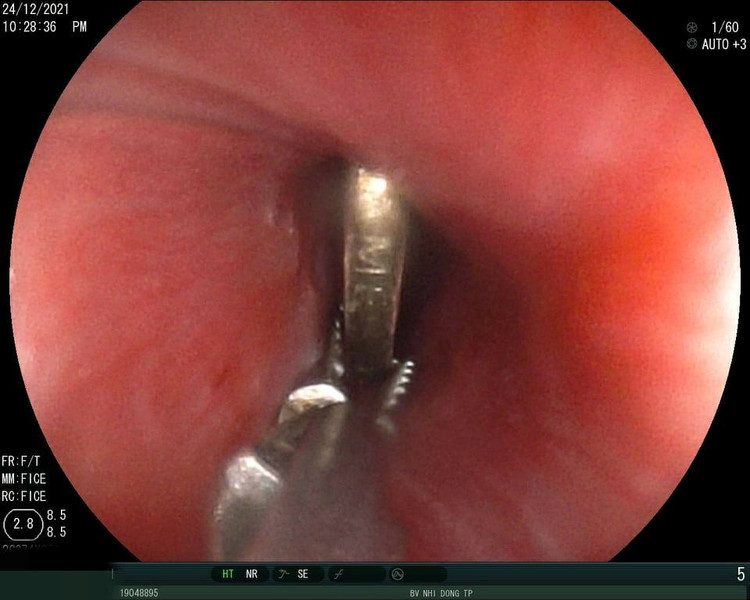

gap-dong-xu-ra-khong-co-hong.jpg

Các bác sĩ đã nội soi, gây mê và gắp kịp thời đồng xu ra khỏi đoạn 1/3 thực quản cho bé.

Đồng xu được lấy ra khỏi cổ họng của cậu bé 5 tuổi.